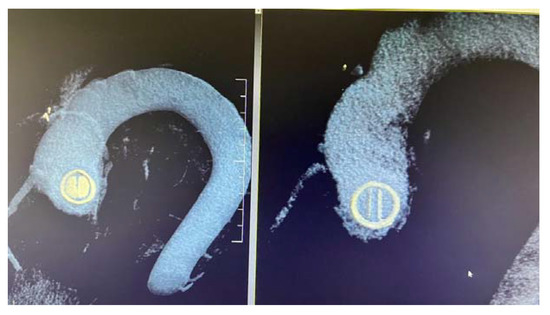

5. Fluoroscopy

Cinefluoroscopy (CF) is a non-invasive, widely available approach to identifying prosthetic valve thrombosis, particularly for patients with bidisc prosthetic valves. The discs may be seen directly, and a tangential view can be used to measure the opening and closing angles. Prosthetic valve thrombosis is characterised by decreased leaflet mobility; these changes mostly depend on how much the prosthetic valve is blocked [23]. Video S4 (Supplementary Material) suggestively demonstrates two cases of prosthetic aortic and mitral thrombosis where indirect signs of valve dysfunction can be measured on fluoroscopic captures.

While fluoroscopy offers the most accurate evaluation of mechanical leaflet motion, it does not allow for the evaluation of soft tissue (such as thrombus or pannus) connected to the valve.

Due to significant artefacts on MDCT, it is preferable to use fluoroscopy or TEE to observe the motion of the leaflets in Bjork–Shiley and Sorin monoleaflet valves [43].

According to Montorsi et al., the sensitivity, specificity, positive and negative predictive values were 87%, 78%, 80%, and 91%, respectively for the diagnosis of prosthetic valve thrombosis in the mitral or aortic position with fluoroscopy [29].

Thrombolytic treatment (TT) has recently been adopted as the initial therapy strategy for the management of prosthetic valve thrombosis. The efficiency of TT has constantly been monitored using TEE. The use of TT for prosthetic valve thrombosis does, however, necessitate a non-invasive technique that may be used repeatedly over time to evaluate therapeutic efficacy. The pressure gradient may be restored in some patients after TT infusion, but they may still exhibit concomitant abnormal leaflet motion at CF, indicating only a partial removal of valve obstruction. The thrombus that is still there might serve as the catalyst for a late thrombotic process if lytic infusion is terminated at this point [22].

In the case of mechanical MVT, MDCT facilitates the evaluation of the valve’s opening and closing angles (Figure 12) and the characterisation of masses attached to the prosthesis and the surrounding tissues [45].

Figure 12.

MDCT. Aortic bidisc mechanical prosthesis in diastole and systole.